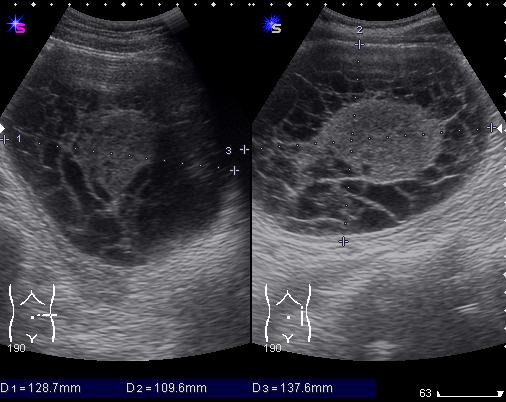

М. 37 лет, жалоб нет, амб. приём, причина назначения УЗИ ОБП: СОЭ 42мм

б\б и м\э консист., как говорится.   Исходит из н\ полюса левой почки